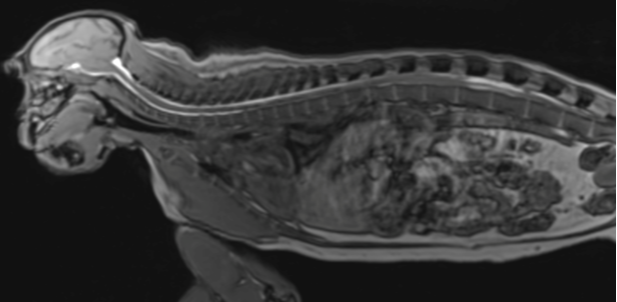

Biodistribution in rodent and non-human primate

Biodistribution in rodent and non-human primate 336